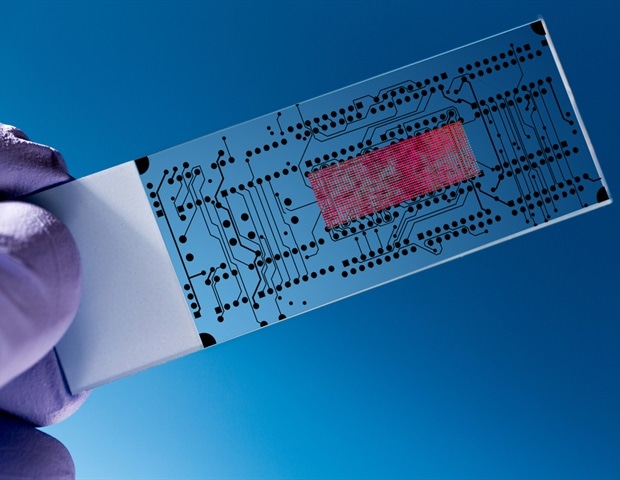

מהנדסי אוניברסיטת סינסינטי יצרו מכשיר חדש שיעזור לרופאים לאבחן דיכאון וחרדה. המכללה להנדסה ומדע יישומי של UC פרופסור למחקר מכובד